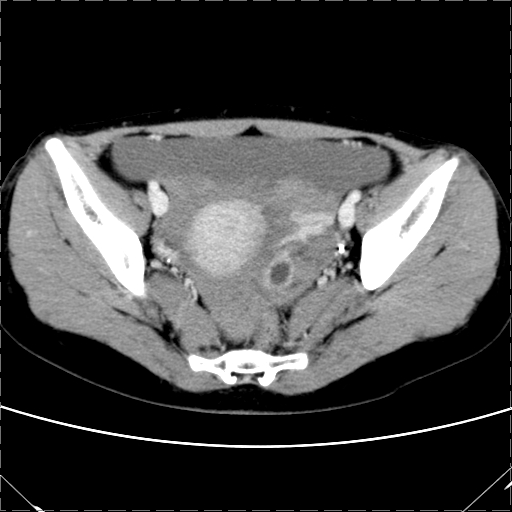

女 29岁 突然腹部疼痛1天 b超示子宫左后方肿块。月经正常。

影像表现复杂,膀胱上见一囊性包块,比膀胱密度高,其内有不均匀稍高密度,似与道格拉斯窝肿物无分界,病灶没有张力,因其腹平坦,推定其具有流动性,但又似见包膜,而b超没有报告这一现象。确实没见过。考虑卵巢囊肿蒂扭转并囊内出血可能。

病变主要位于道格拉斯窝,而且大体形态比较扁平且贴合子宫直肠,无明显张力及对周围脏器压迫,所以考虑为液体,而中间可见囊样病变伴环形强化,期内还可见分隔影,结合突发急性腹痛故多考虑囊腺瘤伴破裂出血。

腹腔镜术后 卵巢黄体囊肿破裂出血